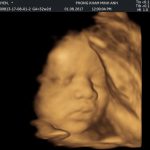

Bạn đã bao giờ thấy em bé mở mắt ngay khi còn trong bụng mẹ chưa???❤️❤️❤️???

Hình ảnh siêu âm 4D của sản phụ Lệ Quyên, 1 trong những sản phụ đã đến khám và nhận quà tại ...

Th7 05, 2018Các mẹ cho ý kiến gì về ảnh của con?

Hình ảnh siêu âm 4D của sản phụ Lệ Quyên, 1 trong những sản phụ đã đến khám và nhận quà tại phòng khám Sản phụ khoa Minh Anh Share this...